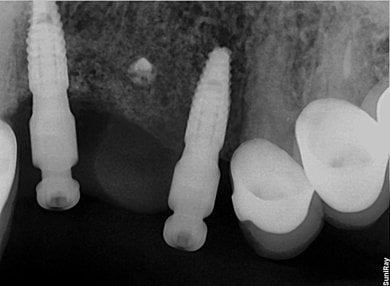

Втрата кісткової маси в області дефекту зуба є одним із найчастіших відносних протипоказань до імплантації зубів. Тим не менш, більшості пацієнтів, 70-90% на верхній щелепі та до 50% на нижній щелепі , перед встановленням дентальних імплантатів потрібне нарощування кісткової тканини.

Встановлення штучного кістково-пластичного матеріалу потрібне тим пацієнтам, у яких зуби відсутні понад два місяці. На жаль, у більшості хворих терміни набагато більші, до 10 років і більше. У таких випадках на допомогу приходять різні процедури кісткової пластики.

Часто в нашій хірургічній практиці зустрічаються стани, коли кістка не готова прийняти дентальні імплантати. За наявності вертикального або горизонтального дефекту потрібна кісткова пластика.

Через деякі причини з часом після видалення зуба об'єм кістки зменшується. Іноді при імплантації зуба необхідно відновити тканину. На допомогу приходить кісткова пластика.

Найчастіше з проблемою відсутності природної кістки стикаються пацієнти, які втратили зуб понад рік тому. Таким чином, тіло зменшує додатковий обсяг кісток, тому що він більше не потрібний. Саме тому стоматологи рекомендують якнайшвидше встановити імплант на місце видаленого зуба.